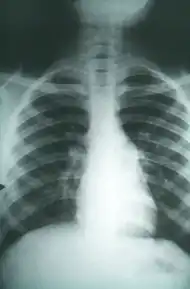

A case of pulmonary fibrosis caused by coccidioidomycosis

Chest X-rays rarely demonstrate nodules or cavities in the lungs, but these images commonly demonstrate lung opacification, pleural effusions, or enlargement of lymph nodes associated with the lungs.[3] Computed tomography scans of the chest are more sensitive than chest X-rays to detect these changes.[3]